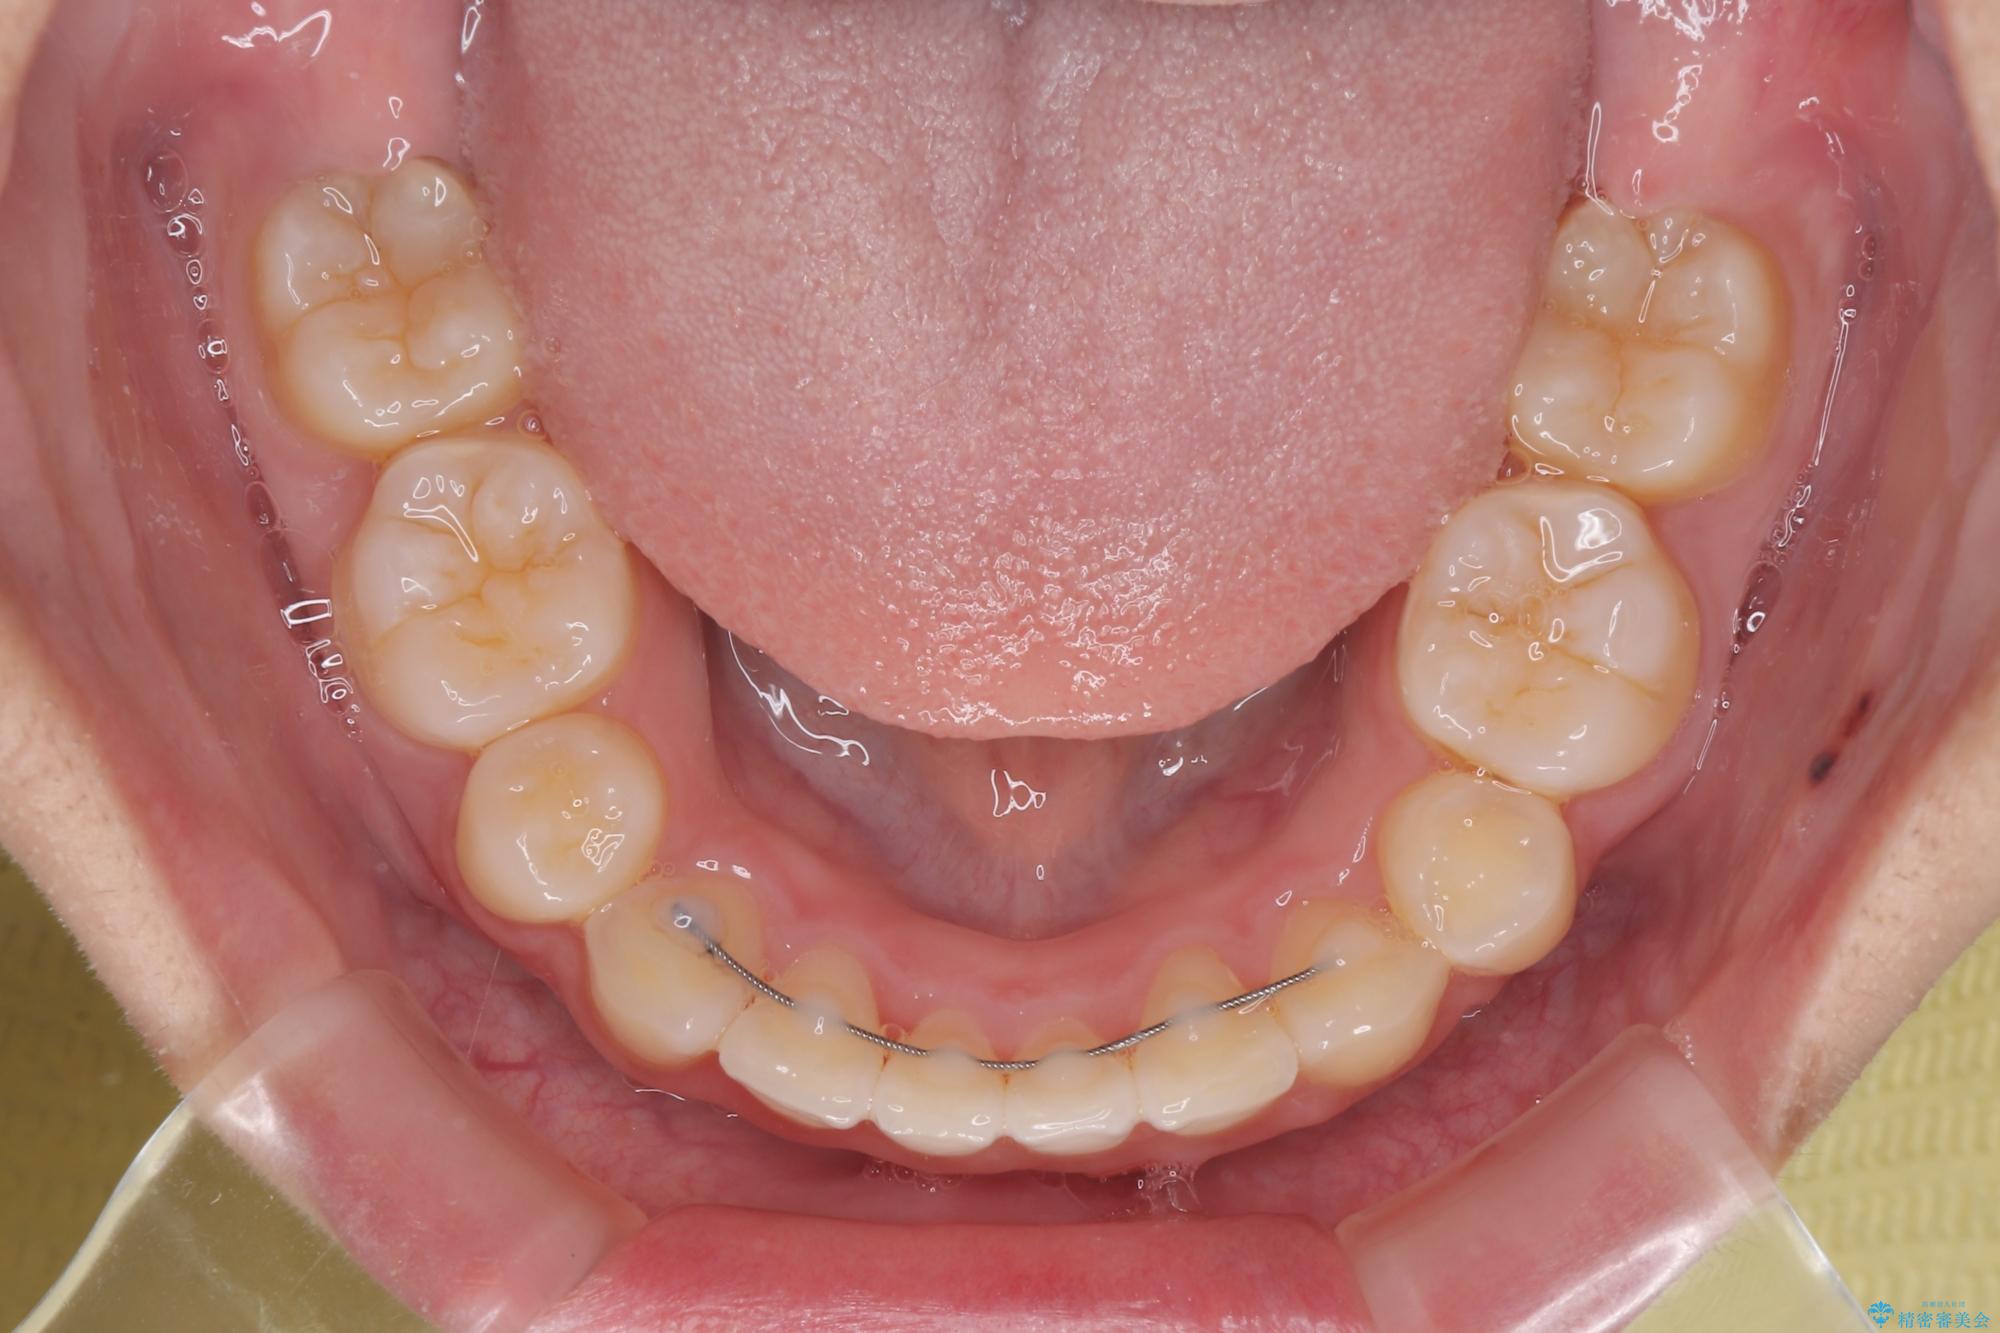

上下正中位置を改善するため、左下はイレギュラーに第二小臼歯を抜歯しました。そのため治療期間の長期化が予想されましたが、2年半ほどで期待通りの歯列に仕上げることができました。